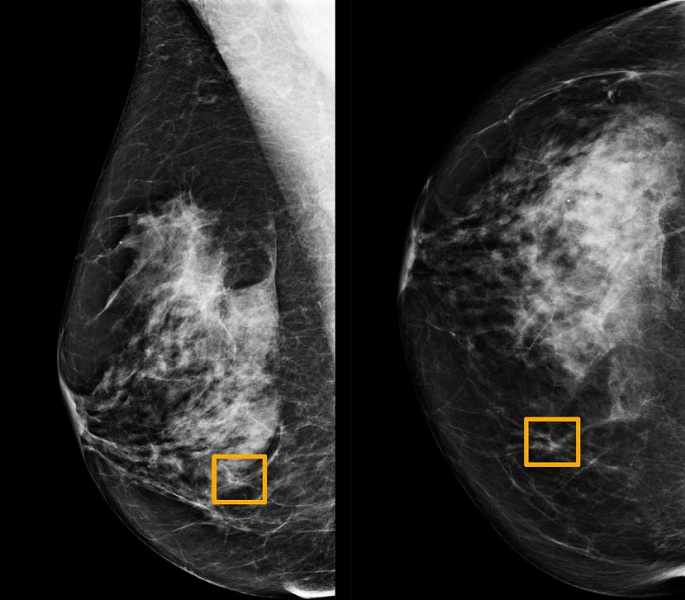

Изучая маммограммы, система искусственного интеллекта Google показала себя не хуже, чем опытные врачи и продемонстрировала перспективу уменьшения количества ошибок.